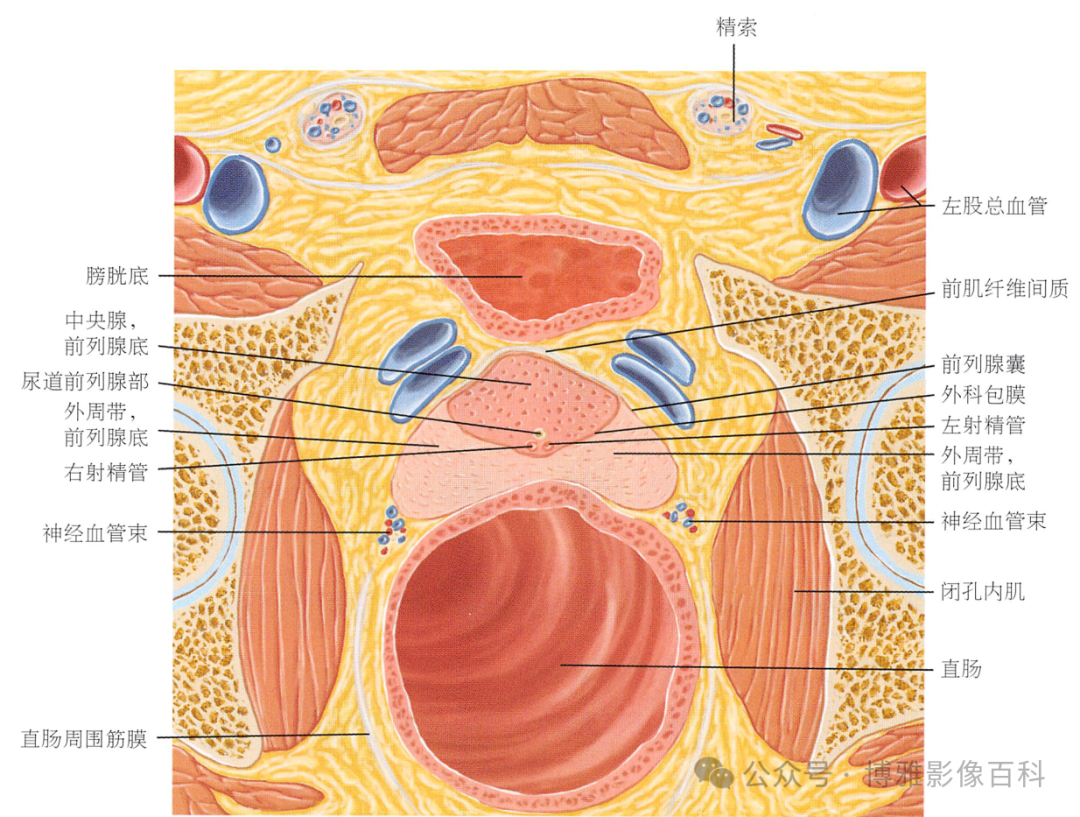

70-75% 的前列腺癌起源于外周带 (PZ)。该区域的后部可以通过直肠指检进行检查。

25% 的前列腺癌起源于移行带 (TZ)。极少数前列腺癌出现在中央带或前纤维肌基质中。

MR 解剖学

前列腺良性增生患者的轴向T2 图像,其他方面正常。外周带是一薄层均匀的高信号,边界清晰连续性的低信号包膜。移行带通常表现为不均匀中等信号,病灶被边界清楚的BPH良性前列腺增生结节所取代。精囊具有均匀T2高信号。未见淋巴结肿大。